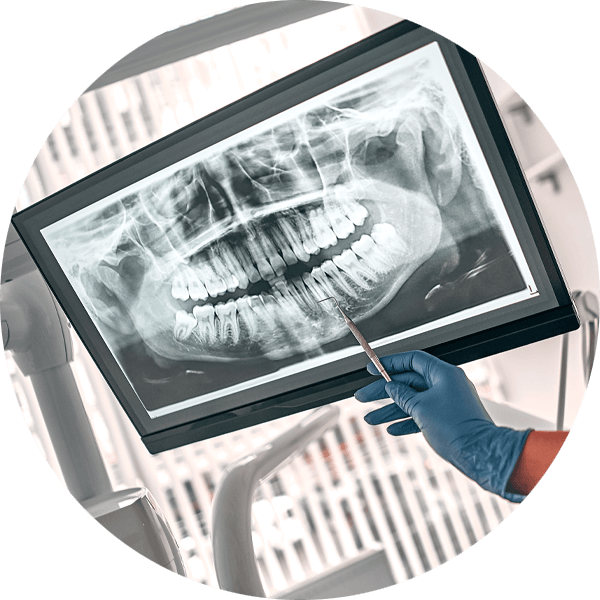

The decision to perform an extraction is typically straightforward when a tooth is impacted by significant decay, severe periodontal disease or a fracture. In addition, impacted wisdom teeth nearly always need to be extracted. Digital X-rays are used to analyze the underlying structures and determine if the tooth can be saved. If there is a pulp infection without a tooth fracture, root canal therapy is a highly successful method for preventing extraction. Extraction of normal teeth may be required for orthodontics, full mouth dental implants or when a primary tooth hasn’t fallen out and is stopping a permanent tooth from erupting. At Kari Mann Dental Studio in Cape Coral, our goal is always to save natural teeth, however, if conservative treatment is ineffective, extraction may be necessary. Extraction of a damaged or abscessed tooth can prevent more serious issues from impacting other teeth, your oral health and even your physical health. Regardless of the reason, Dr. Kari Mann has extensive expertise performing gentle tooth extraction in Cape Coral, FL. With a local anesthetic and sedation if you need it, tooth extraction will alleviate acute or chronic tooth pain and restore your oral health.

Tooth pain - X ray image

dental xray